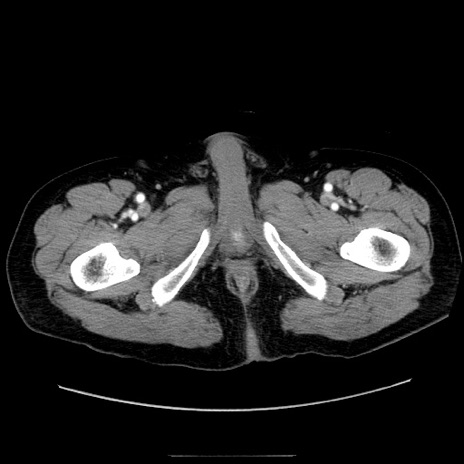

症例30(横断像)

【症例】80歳代男性

【現病歴】約6時間前から臍下部痛が出現。次第に腹部膨隆・背部痛も生じてきたため来院。背部痛の場所は変化しない。

【身体所見】意識清明、BT 36.3℃、BP  131/87mmHg、P 87bpm、SpO2 100%(RA)、臍周囲自発痛・圧痛あり、反跳痛なし、自発痛部位に一致して板状硬あり、腹部膨隆、腸雑音減弱、CVA tenderness両側陰性。